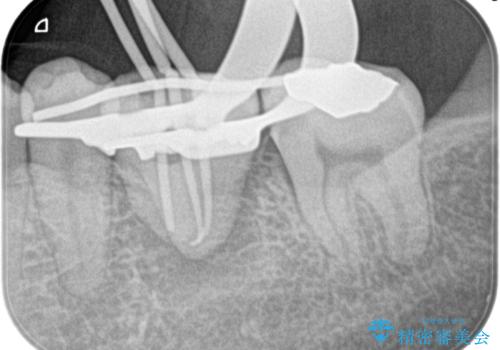

移植歯はアンキローシス(歯と歯槽骨の間の歯根膜がなく、歯の根と骨が結合している状態)するリスクがあります。

アンキローシスを避けるため、術中や術後管理に注意が必要です。